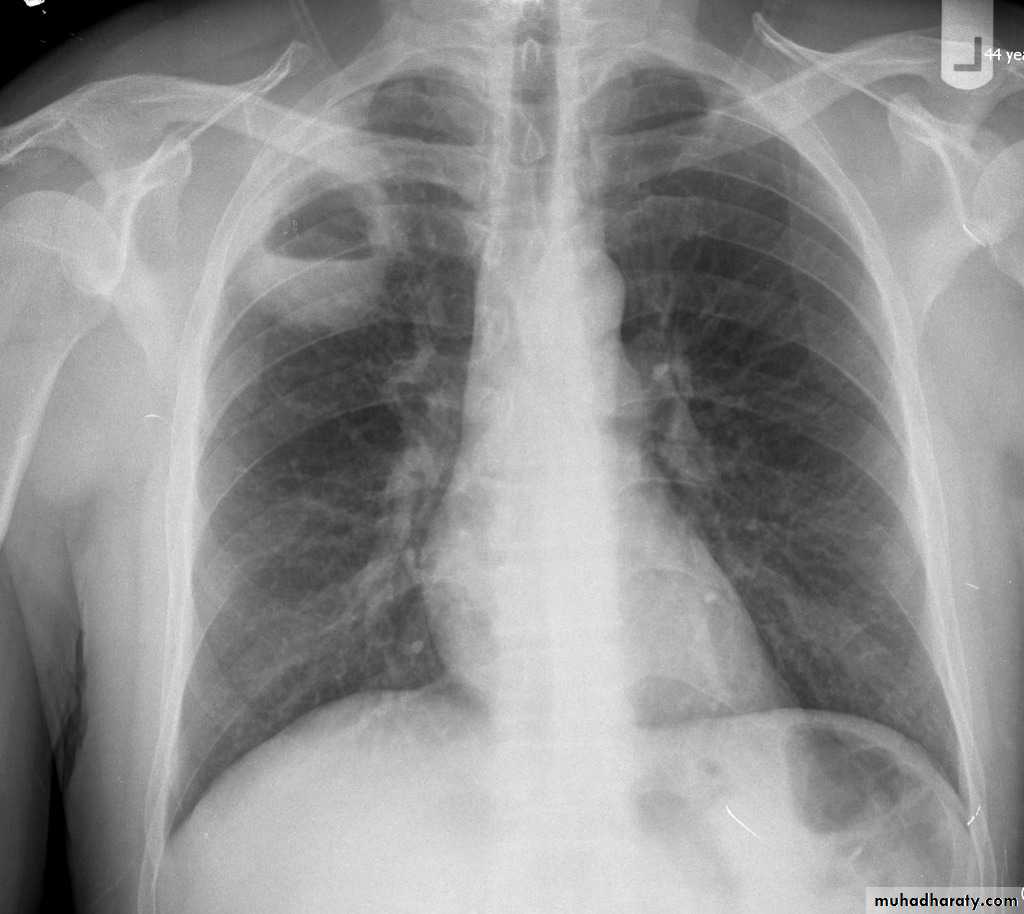

Plain radiograph

Chest x-rays are usually abnormal

1. Tram-track opacities are seen in cylindrical bronchiectasis, and

2. air-fluid levels may be seen in cystic bronchiectasis.

Honey comb shadow

3.Overall there appears to be an increase in bronchovascular markings, and bronchi seen end on may appear as ring shadows .

4.Pulmonary vasculature appears ill-defined, thought to represent peri bronchovascular fibrosis .